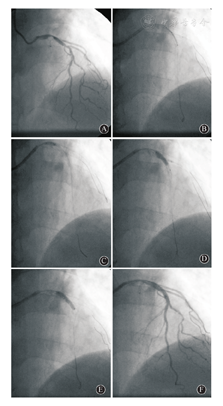

所有患者常规采用右桡动脉行冠状动脉造影检查,符合介入治疗指征者,随机分为拘禁导丝组和拘禁球囊组。拘禁导丝组采用常规边支导丝保护技术,JBT组:(1)应用6F或7F指引导管到位,两根导丝分别送到主支和分支远端,边支一般采用非亲水涂层导丝;(2)常规预扩主支病变,选择直径及长度合适的支架先送入主支;(3)在边支送入小于边支直径0.5 mm的单轨球囊(通常1.5~2.0 mm),边支球囊近端突出至主支约2 mm;(4)先低压力膨胀分支球囊,压力通常小于6 atm(一般为4~6 atm),接着再以6~8 atm膨胀主支支架,球囊与支架"对吻";(5)撤出分支球囊,保留分支导丝,同时注意保留支架球囊不要移位;(6)支架内球囊再次于支架内以12~14 atm高压扩张支架;(7)重复行冠状动脉造影检查,如结果良好则撤出主支及边支导丝;若提示边支夹层、血流明显受限、狭窄程度在原基础上超过20%、患者有临床症状或血流动力学有变化,可操作导丝穿主支支架网眼进入边支后再撤出边支的拘禁导丝,并根据实际情况进行边支球囊扩张或支架置入,所有穿网眼边支球囊扩张或支架置入的病例均需对吻后扩张。具体手术操作见图1。

A:前降支与对角支成分叉病变;B:两根导丝分别进入前降支和对角支,并常规预扩主支病变;C:先送入主支支架,后送入边支球囊,边支球囊近端突出至主支约2 mm;D:先低压力膨胀分支球囊,再以6~8 atm膨胀主支支架,球囊与支架"对吻";E:回撤边支球囊后再次扩张主支支架;F:造影示对角支血流未受影响